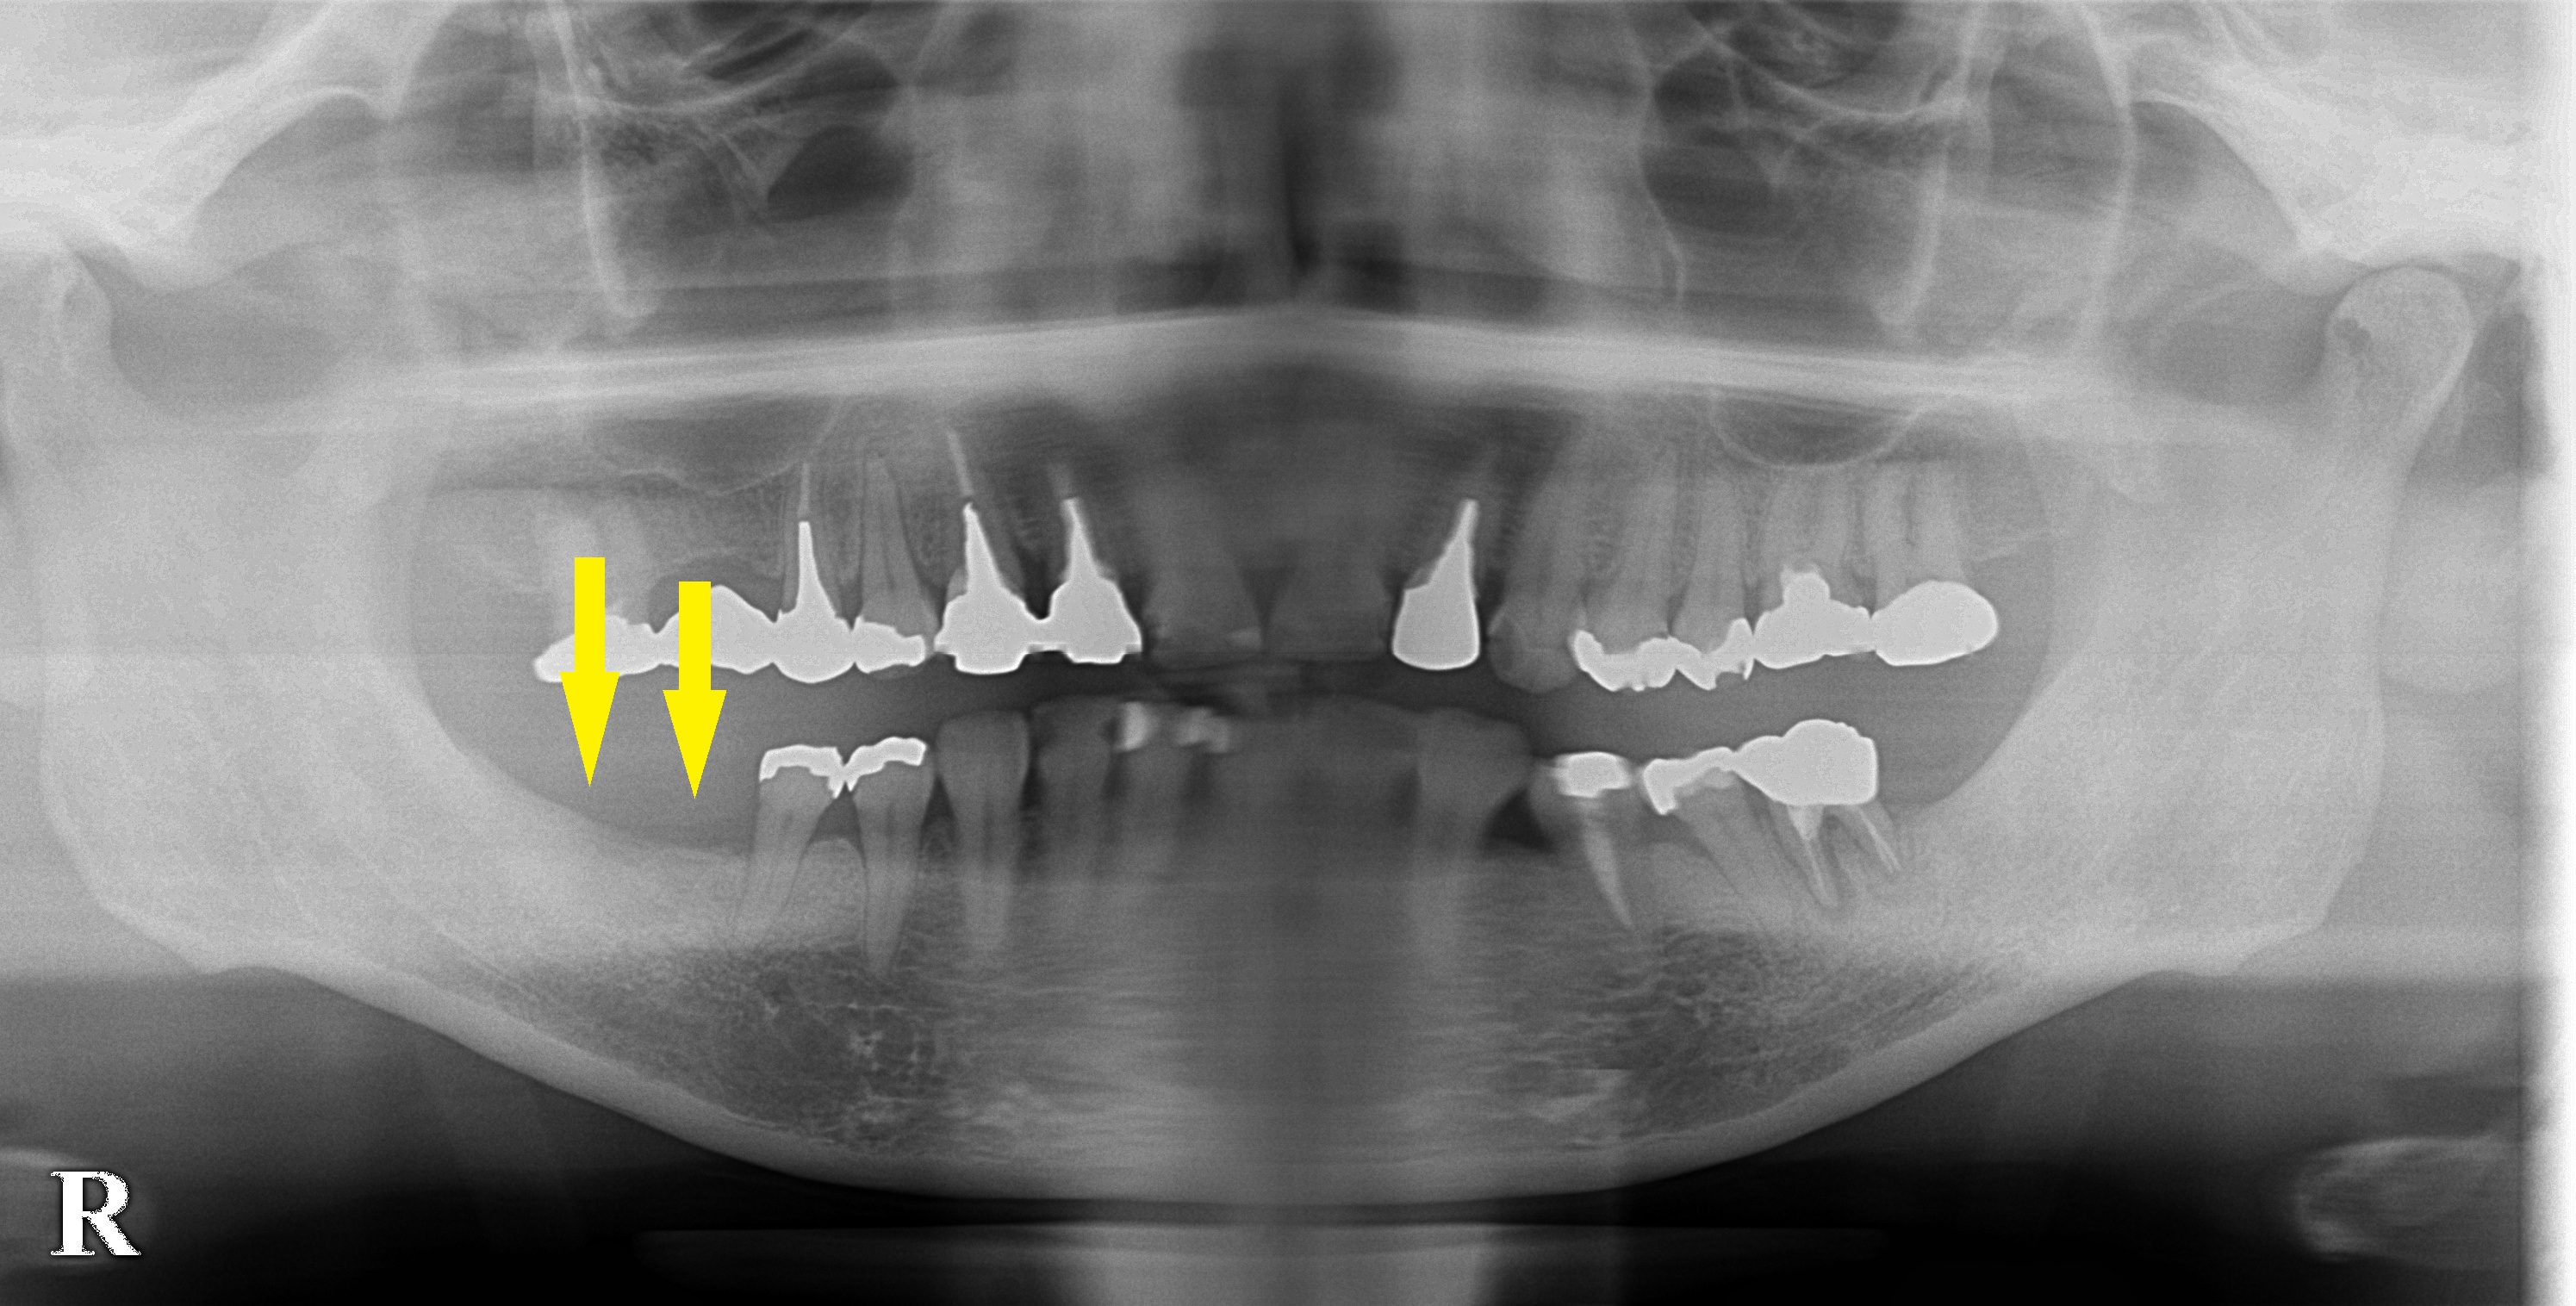

数年前から右下顎大臼歯が2本ないままの状態で過ごされてきたそうです。

歯が抜けてから数年経過しており骨量も十分でしたので、

本日2本のインプラント埋入術を行ないました。